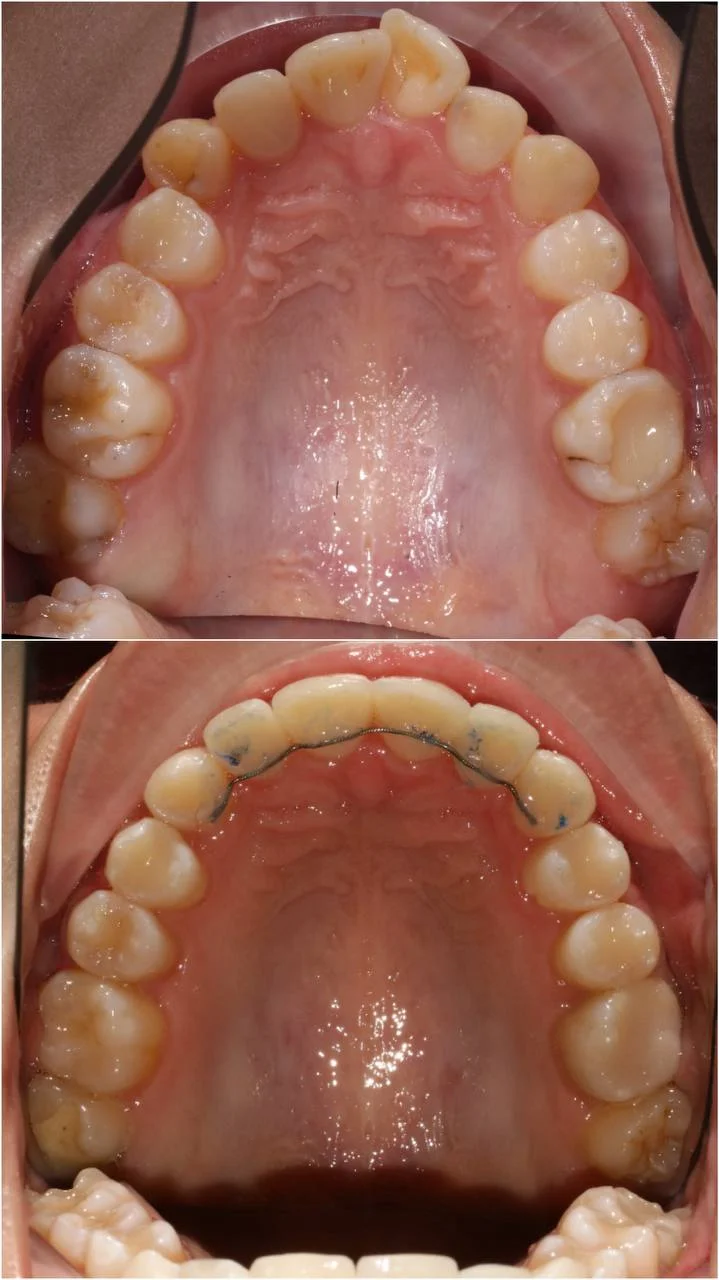

Зубы выровнены, смыкание нормализовано. Установлены несъёмные ретейнеры на обе челюсти, изготовлены ретенционные капы. Пациентка предварительно проконсультирована ортопедом онлайн.

Решение: Поставили элайнеры 3D Smile на обе челюсти. Лечение заняло 4 года и потребовало нескольких последовательных этапов коррекции. Капы менялись каждые 1–2 недели, на контрольных визитах отслеживали прогресс и выдавали новые наборы. Зубы встали в правильное положение, смыкание нормализовалось. Зафиксировали ретейнеры на обе челюсти, изготовили ретенционные капы. Пациентка прошла онлайн-консультацию с ортопедом для оценки дальнейших шагов.

Лечение потребовало нескольких последовательных этапов — каждый дозаказ кап уточнял положение зубов, которые не полностью отреагировали на предыдущий курс. Элайнеры 3D Smile позволяют работать поэтапно, корректируя план по ходу. Результат получен, ретейнеры зафиксированы. Рекомендовала пациентке консультацию ортопеда для оценки состояния зубов после лечения